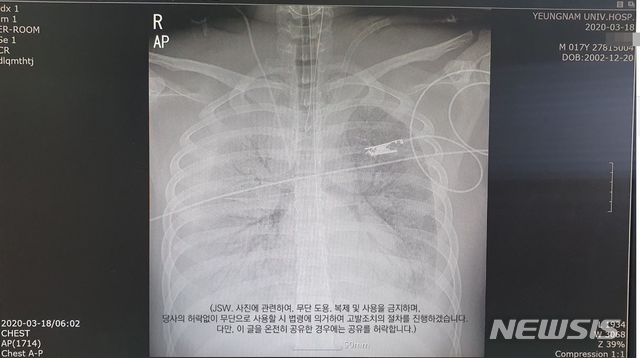

![[대구=뉴시스]이은혜 기자 = 대구에서 폐렴 증세를 보이다 숨진 17세 소년의 폐 엑스레이 사진. 2020.03.26. (사진=유가족 페이스북 캡처) photo@newsis.com](https://img1.newsis.com/2020/03/26/NISI20200326_0000501823_web.jpg?rnd=20200326163934)

[대구=뉴시스]이은혜 기자 = 대구에서 폐렴 증세를 보이다 숨진 17세 소년의 폐 엑스레이 사진. 2020.03.26. (사진=유가족 페이스북 캡처) [email protected]

17세 소년 A군의 친형 B씨는 26일 오후 자신의 페이스북에 A군 폐 엑스레이(X-ray) 사진과 대구 영남대병원 진료비 영수증을 게시했다.

B씨는 "최근 가슴 아픈 일로 세상을 떠난 대구 만 17세의 첫째 형이다"라며 "병원비 청구 관련해 궁금해하는 분들이 많으셔서 영수증 사진을 첨부한다. 그리고 요일별 X-ray 사진과 CT사진을 첨부한다"고 했다.

이어 "의료 관련된 분 중 제 동생의 당시 증상과 사인을 판단해주실 분이 계시다면 판독 좀 부탁드린다"며 "정확한 사인에 대한 판단을 의료진에게 부탁하고자 글과 사진을 업로드했다"고 썼다.